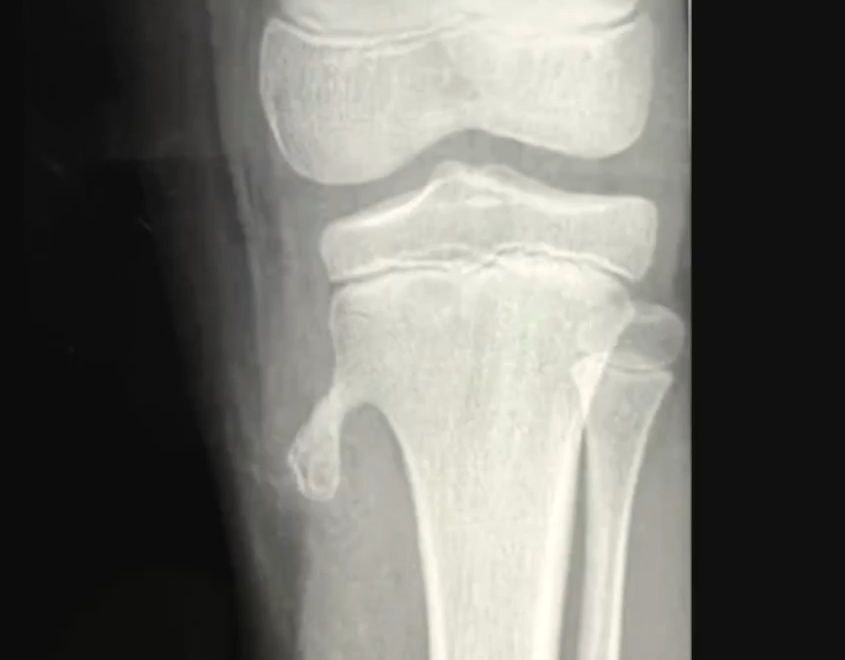

Как выглядят остеофиты и экзостозы?

В классической парадигме остеофиты и экзостозы рассматриваются как патологический процесс, что-то пошло не так, и сформировался нарост.

На картинках мы видим, что как будто выросла новая кость, маленькая косточка отпачковывается от большой.

Можно предположить, что это некая неоплазия, новое образование, иначе говоря. То есть клетки вдруг решили избыточно поделиться. И так как это кальцифицированное образование, то мы могли бы предположить, что это избыток кальция, как это сейчас рассматривает традиционная парадигма. Но она не объясняет, почему экзостоз вырос именно в этом месте и почему именно сейчас? Что вообще там происходило? Это объясняет только моя любимая парадигма ГНМ. Германская новая медицина мне позволила абсолютно полностью понять природу остеофитов и экзостозов и разобраться, что вообще с этим всем делать и делать ли.